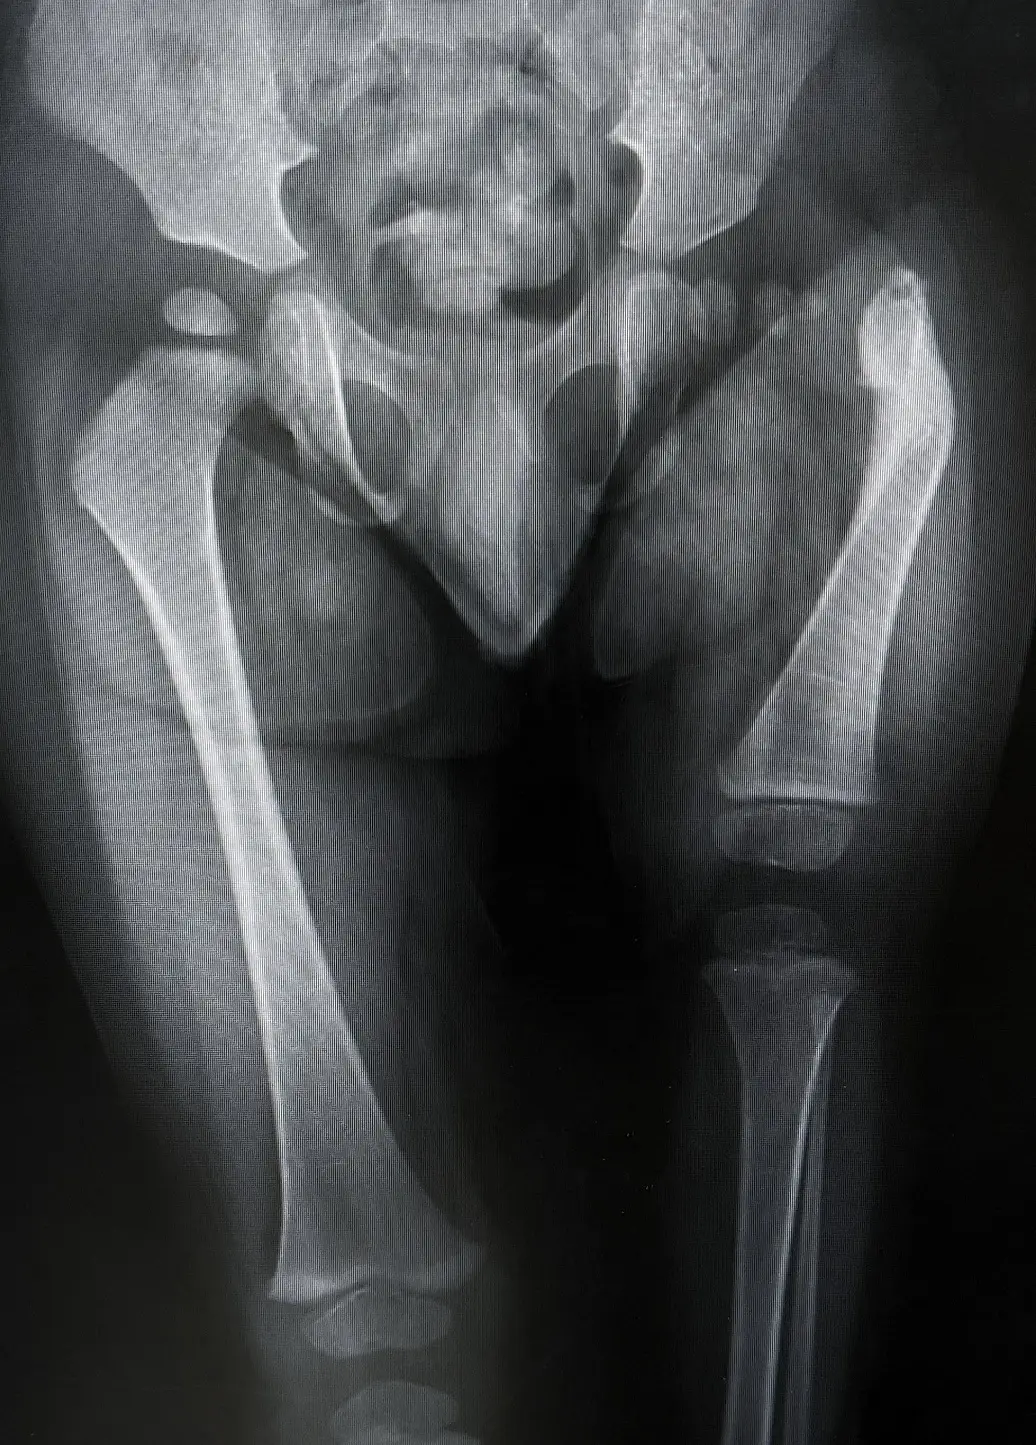

Proximal femoral focal deficiency (PFFD) is a condition where a child is born with a shortened or incomplete thigh bone. The word "proximal" means the part of the bone closest to the hip, where the defect usually starts. Even though the foot and lower leg might look normal, they sit much higher up because the femur didn’t grow to its full length. As a result, this may make the hip and knee joints weak or unstable.

Medical professionals generally use the Aitken Classification to categorize the severity of proximal femoral focal deficiency (PFFD). This system uses four distinct categories:

- Class A: The femoral head is present within the hip socket. A short femur exists, but a bony or cartilaginous connection remains between the hip and the shaft.

- Class B: The femoral head is present, and the hip socket (acetabulum) is well-formed, but there is no bony connection between the femur and the hip joint.

- Class C: The hip socket is severely underdeveloped, and the femoral head is either absent or fails to harden into bone. The femur itself is significantly shortened.

- Class D: The most severe form, characterized by the complete absence of the hip joint and the proximal femur. Only a small portion of the bone near the knee may remain.

Diagnosing proximal femoral focal deficiency (PFFD) often starts during prenatal ultrasound scans. After birth, doctors confirm the condition through:

- X-ray imaging: Determination of the presence of the femoral head and the state of the hip socket.